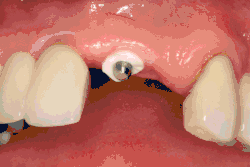

Single tooth implant restoration

Single tooth restorations are individual freestanding units not connected to other teeth or implants, used to replace missing individual teeth.[10] For individual tooth replacement, an implant abutment is first secured to the implant with an abutment screw. A crown (the dental prosthesis) is then connected to the abutment with dental cement, a small screw, or fused with the abutment as one piece during fabrication.[14]: 211–232 Dental implants, in the same way, can also be used to retain a multiple tooth dental prosthesis either in the form of a fixed bridge or removable dentures.